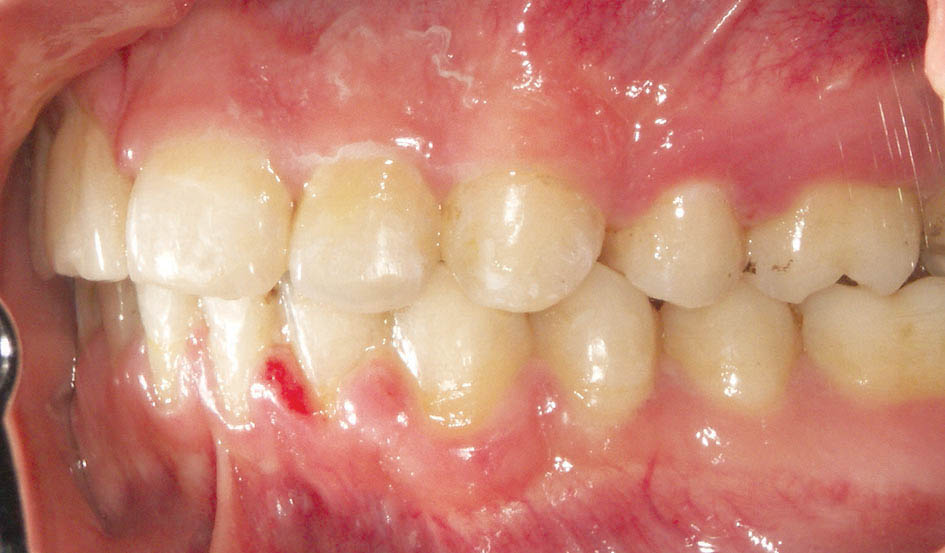

در زمان بستن فضا محل اعمال نیرو روی ناحیه خلفی، باکال تیوب مولر اول است، لذا باکال آن بیشتر مزیاله و سمت لینگوال کمتر مزیاله میشود. این بدان معنی است که در حین بستن فضا مولر اول دچار چرخش میشود، لذا بعد از مدتی دیگر فضا بسته نمیشود (شکل 23-3). در موارد کشیدنی برای جلوگیری از این حالت حتماً باید دندان هفت را بچسبانید تا انتهای سیم درون تیوب هفت باشد.

شکل 23-3: نیروی بستن فضا روی مولر اول باعث چرخش آن شده است. چسباندن براکت مولر دوم و قرار دادن سیم درون آن مانع چرخش مولر اول در زمان بستن فضا میشود.

انتهای سیم انعطاف پذیری بالایی دارد، لذا اگر تا مولر اول چسبانده باشید و Active Tieback را به آن بزنید بخاطر انعطاف بالای سیم، مولر اول سریع دچار چرخش میشود. اگر تا مولر دوم بچسبانید و سیم درون باکال تیوب مولر دوم باشد در این صورت وسط سیم درون باکال تیوب مولر اول قرار خواهد داشت که انعطاف کمتری دارد، لذا کمتر دچار چرخش میشود. چرخش مولر اول یک مانع اصلی در زمان بسته شدن فضا است و بدین صورت با قراردادن انتهای سیم درون مولر دوم باعث بسته شدن راحت فضا میشویم.